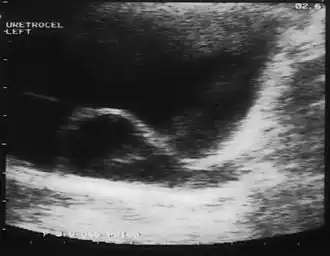

Уретероцеле

Уретероцеле — сужение устья мочеточника, приводящее к образованию шаровидного и кистовидного выпячивания (грыжеподобного) внутрипузырного отдела мочеточника, состоящего из двух слоёв слизистой оболочки — внутри мочеточника и снаружи мочевого пузыря, ввиду чего происходит нарушение оттока мочи и возникновение уретрогидронефротической трансформации и хронического пиелонефрита[2].

Диагностика сводится к экскреторной урографии (внутривенное введение рентгеноконтрастного вещества), УЗИ почек или мочевого пузыря, цистография, цистоскопия[5].